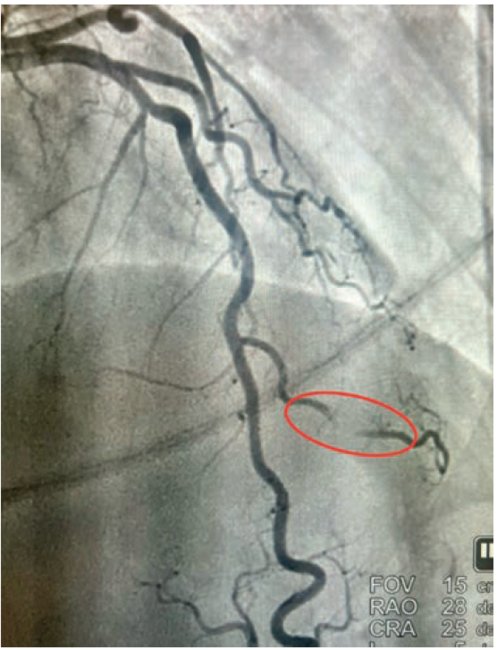

• Cardiac catheterization: Catheterization revealed normal coronary arteries with severe systolic compression of the second diagonal branch (Figures 1-2; Video).

Given the fact that the patient continued to have recurrent episodes of ventricular tachycardia, along with elevated troponin, and an echocardiogram showing reduced LVEF with slightly more pronounced hypokinesis of the septal and apical walls, the decision was made to rule out ischemia as a possible cause. She subsequently underwent coronary angiography via right radial approach, which revealed a right-dominant system and normal coronary arteries, with the exception of the 2nd diagonal branch of the LAD, which had severe systolic compression, resulting in near-obliteration of the artery with each cardiac cycle (Video).